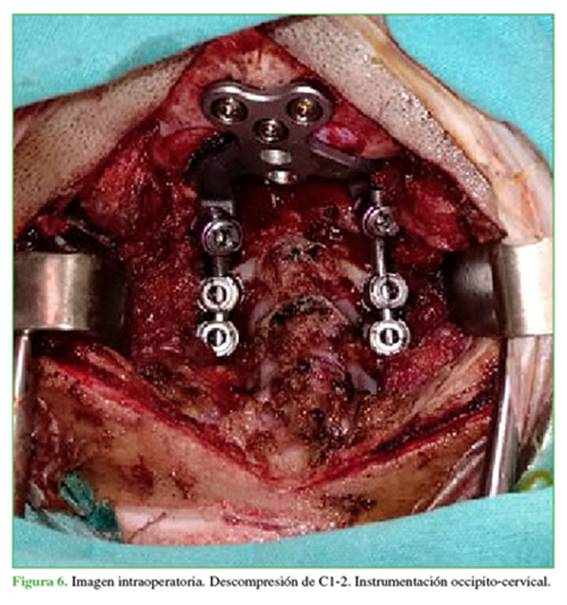

En junio de 2021, se procedió a realizar una artrodesis de C0-C4 con laminectomía de C1 y C2, y ampliación del foramen magno (a cargo del servicio de neurocirugía). Se colocó un halo chaleco de protección (Figura 6).

El abordaje debe realizarse sin maniobras intempestivas, con un control minucioso del sangrado, ya que la presión ocasionada sobre los cuerpos vertebrales para ingresar a liberar o a colocar los tornillos aumenta la presión intracanal y puede provocar trastornos neurológicos. Durante el procedimiento, se encontraron arcos posteriores de C1 y C2 hipoplásicos; durante las maniobras de descompresión (tanto a nivel de C1 como del foramen magno), la paciente tuvo episodios de bradicardia extrema con caída de potenciales y recuperación parcial al finalizar la descompresión. Luego del procedimiento, la paciente ingresó intubada en la unidad de terapia intensiva pediátrica.